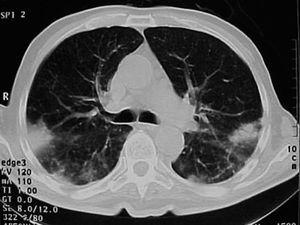

Varón de 74 años, ex fumador de 37 paquetes-año, sin alergias conocidas, diagnosticado de ELA hacía 10 meses y en tratamiento con Rilutek® (riluzol), a dosis de 50 mg/12 h, desde hacía 5 meses, que 45 días antes del ingreso en nuestro centro había iniciado un cuadro clínico consistente en tos no productiva. Inicialmente había recibido tratamiento con amoxicilina-ácido clavulánico a dosis de 875 mg-125 mg/8 h durante 18 días, hasta 5 días antes de su ingreso, con progresivo deterioro clínico consistente en incremento de la tos no productiva, disnea de reposo, astenia, sudación profusa, taquipnea, sin objetivar fiebre durante todo el período de evolución del proceso. En la exploración efectuada en el momento del ingreso hospitalario estaba afebril, con una presión arterial de 110/60 mmHg, frecuencia cardíaca de 94 lat/min y frecuencia respiratoria de 24 respiraciones/min. Se apreció una disminución de la amplitud de los movimientos respiratorios sin otros hallazgos de interés. La gasometría arterial con oxígeno en gafas a 2 l/min mostró los siguientes valores: pH de 7,46, presión arterial de oxígeno de 67 mmHg, presión arterial de anhídrido carbónico de 44 mmHg y HCO3 de 31 mEq/l. En la analítica, el hemograma presentó 6.200 leucocitos (un 68% neutrófilos y un 1% eosinófilos) y una velocidad de sedimentación globular de 74 mm en la primera hora. Existía elevación de las cifras de fibrinógeno (715 mg/dl), inmunoglobulina (Ig) G (1.960 mg/dl; IgG1: 1.310 mg/dl; IgG4: 280 mg/dl), IgA (498 mg/dl), IgE (299 KU/l) y proteína C reactiva (20 mg/l). El resto de las determinaciones analíticas, incluidos los parámetros hematológicos, glucemia, iones, parámetros de función renal, hepáticos, lactatodeshidrogenasa y sus isoenzimas, enzima de conversión de la angiotensina, IgM, anticuerpos antinucleares, anti-ADN, anticuerpos anticitoplasma de neutrófilo y marcadores tumorales séricos, estaban dentro de los valores considerados normales. La prueba de Mantoux, las serologías frente a gérmenes atípicos y virus respiratorios, así como las determinaciones en orina para Legionella pneumophila serotipo 1 y Streptococcus pneumoniae, fueron negativas. A pesar de estar afebril, durante su ingreso se extrajeron hemocultivos, sin que se aislara ningún germen. El paciente no expectoraba, por lo que no se pudieron obtener muestras para procesamiento bacteriológico. El electrocardiograma y un ecocardiograma no objetivaron anomalías. Las pruebas cutáneas a una batería de neumoalergenos habituales, entre ellos ácaros, pólenes de malezas, árboles, gramíneas, hongos y epitelios, fueran negativos. La radiografía y la tomografía computarizada de tórax mostraron infiltrados alveolointersticiales bilaterales (figs. 1 y 2).

Fig. 1. Infiltrados pulmonares bilaterales de predominio periférico.

Dada la ausencia de fiebre, leucocitosis y semiología de infección respiratoria, se sospechó que la afectación pulmonar podía ser secundaria al riluzol, único fármaco que recibía el paciente. Se retiró el medicamento y se inició tratamiento con 40 mg diarios de metilprednisolona durante 6 días, al cabo de los cuales se interrumpió. A las 72 h ya era manifiesta la disminución del grado de disnea, de la astenia y de los infiltrados, así como el incremento de la saturación de oxígeno. Al cabo de una semana los infiltrados habían desaparecido y la espirometría mostraba los siguientes valores: capacidad vital forzada (FVC) de 1,34 l (33%), volumen espiratorio forzado en el primer segundo (FEV1) de 1,32 l (47%) y FEV1/FVC del 99%. La saturación de oxígeno basal era del 95% y no había desaturación en el test de la marcha de los 6 min. Posteriormente, en el seguimiento realizado no reaparecieron los infiltrados y el paciente falleció al cabo de 8 meses debido a la ELA.